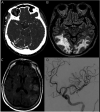

Results: Seventy-four patients were identified (42/57% male, median age 64 years). The majority of patients self-identified as Black or African American (38, 51%). The most common neurologic symptoms at presentation to the hospital included altered mental status (39, 53%), fatigue (18, 24%), and headache (18, 18%). Fifteen patients had ischemic strokes (20%). There were 10 in-hospital mortalities, with moderately severe disability among survivors at discharge (14%, median modified Rankin Scale score of 4).

Conclusions: Neurologic findings spanned inflammatory, vascular pathologies, sequelae of critical illness and metabolic derangements, possible direct involvement of the nervous system by SARS-CoV-2, and exacerbation of underlying neurologic conditions, highlighting a broad range of possible etiologies of neurologic complications in patients with coronavirus disease 2019 (COVID-19). Further studies are needed to characterize the infectious and postinfectious neurologic complications of COVID-19 in diverse patient populations.